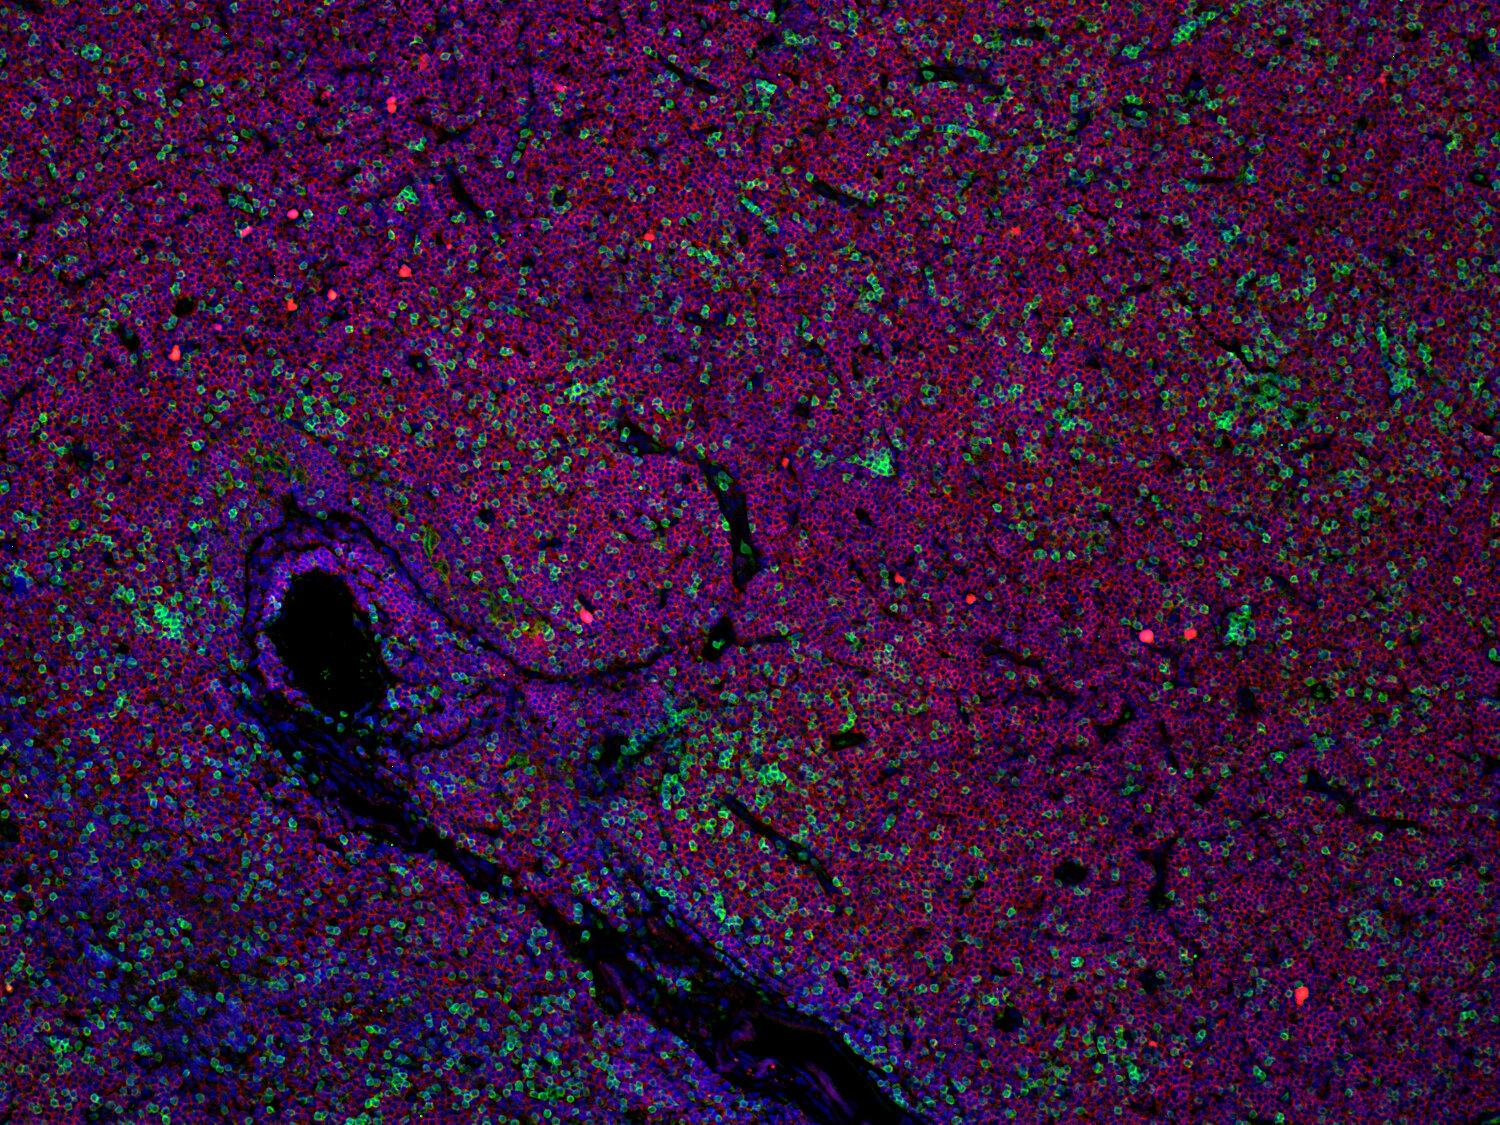

Immunofluorescence image of a human FFPE tonsil section stained for CD19 (B cells, red) and CD3e (T cells, green)